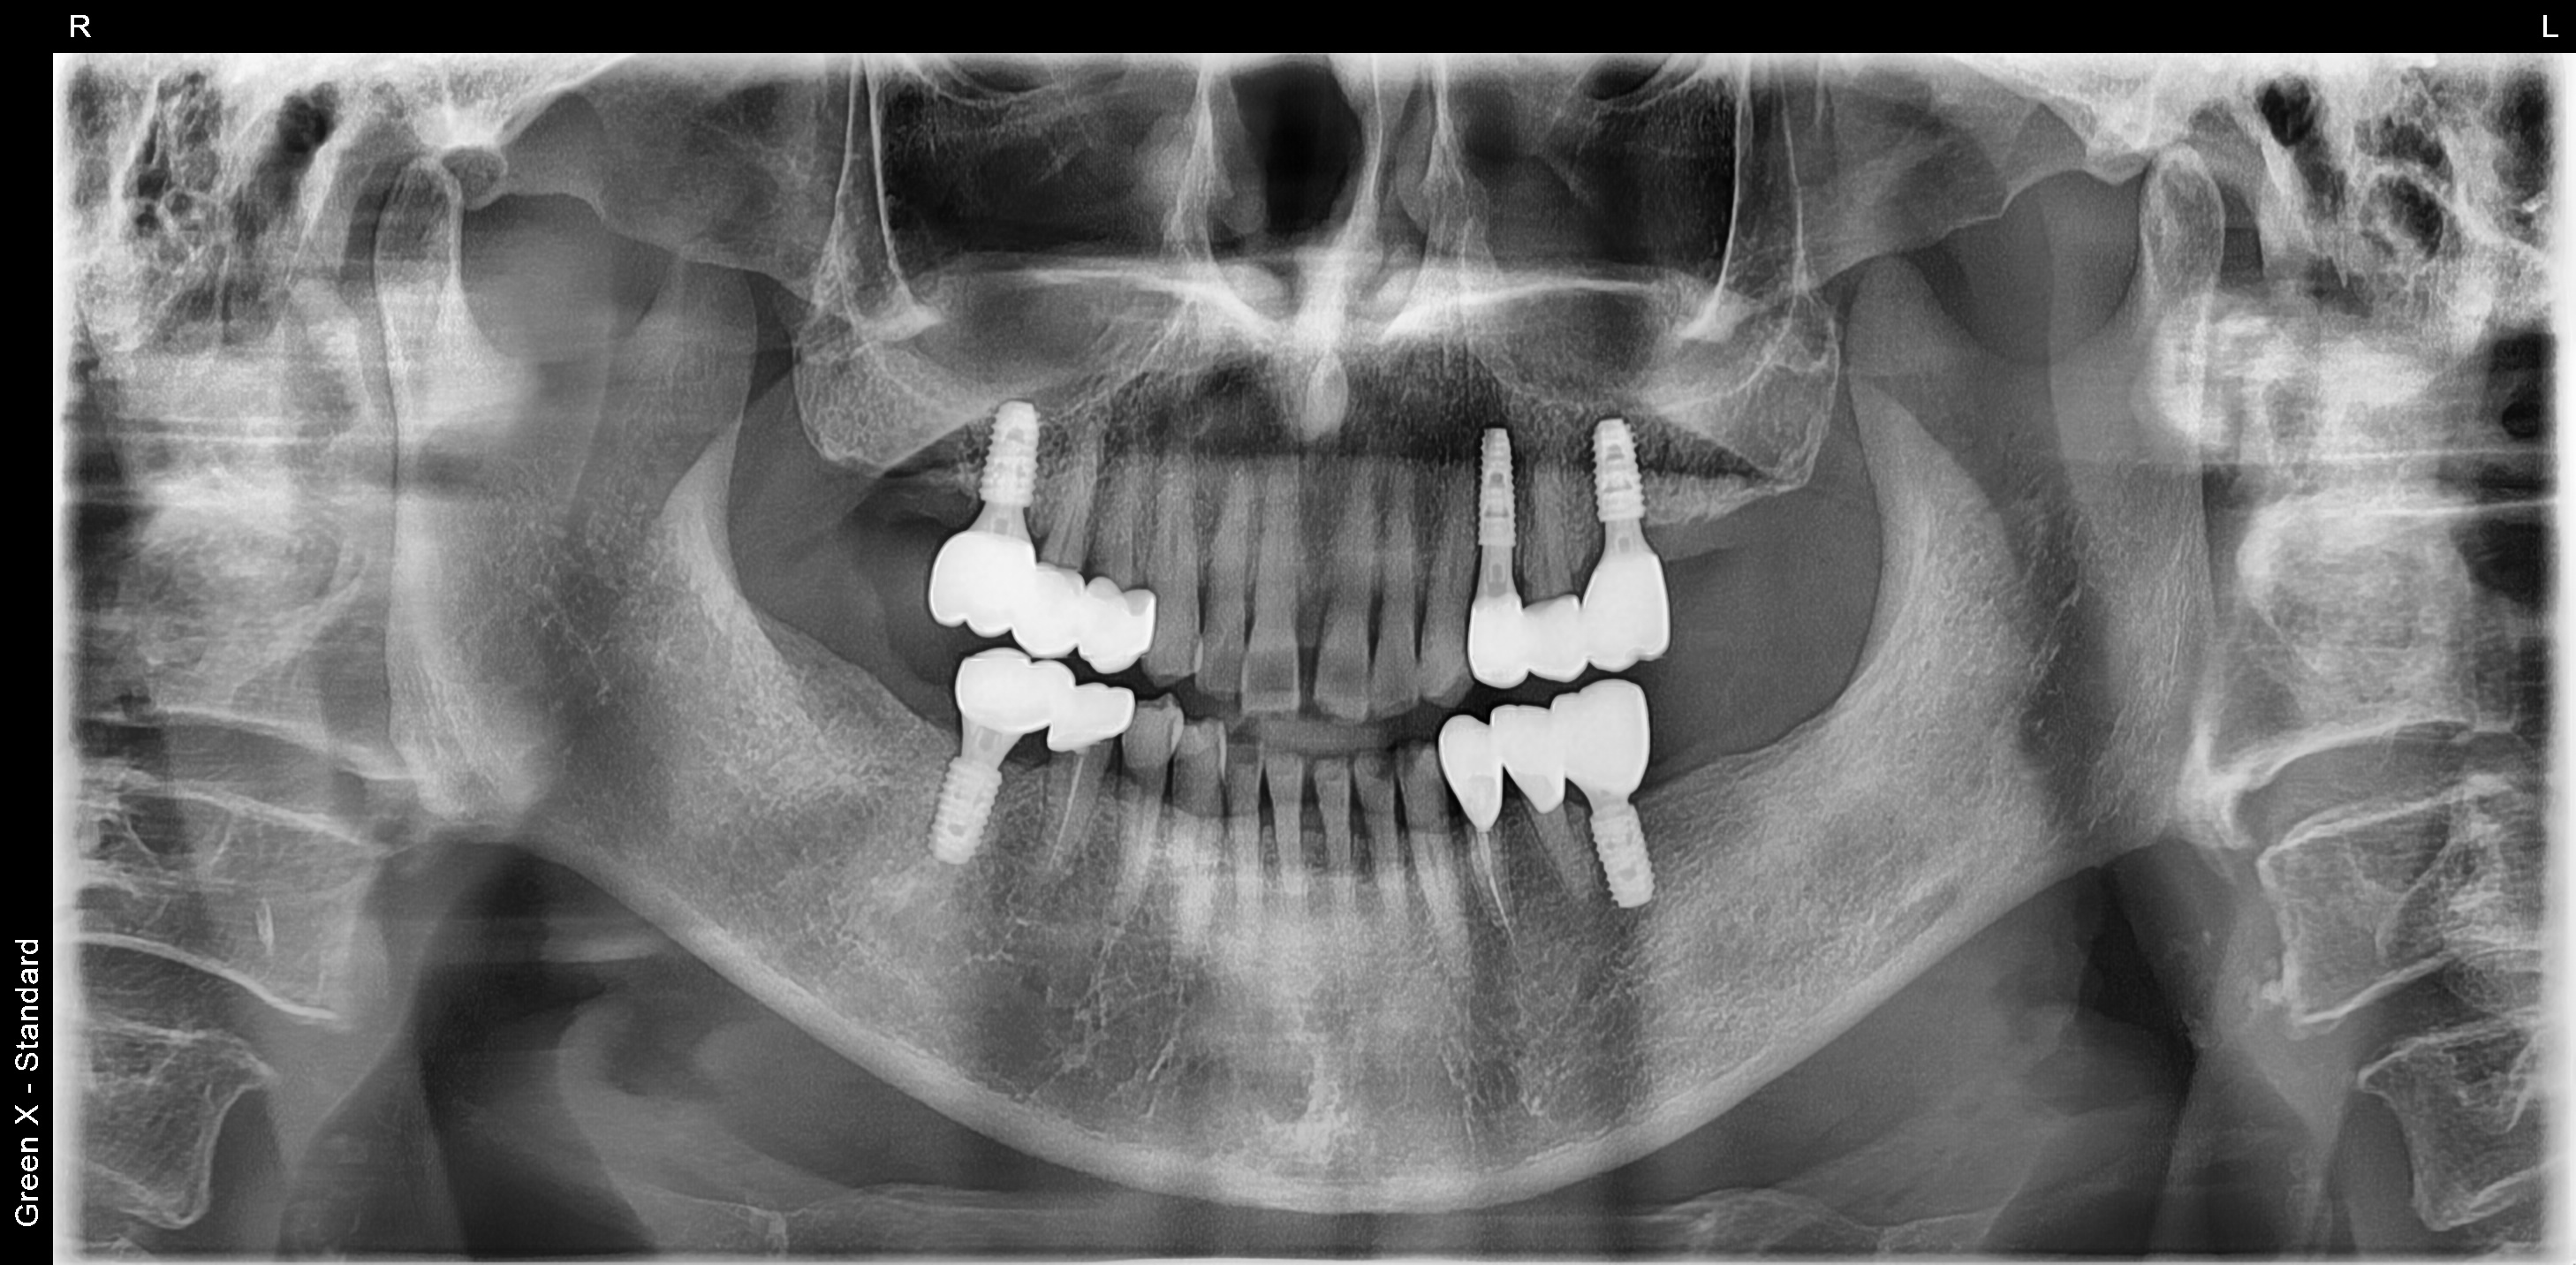

김포 서울케이치과에서 진행한 어금니 다수치아 임플란트 사례입니다.

심한 충치로 인하여 뿌리만 남은 어금니로 인하여 식사가 불편하셨던 50대 남성 환자분이 소개로 내원하셨습니다.

경제적인 이유로 첫번째 어금니까지만 임플란트를 식립하셨고, 6개의 작은 어금니는 심한 파절과 마모로 크라운 치료를 하였습니다.

<치료 후>